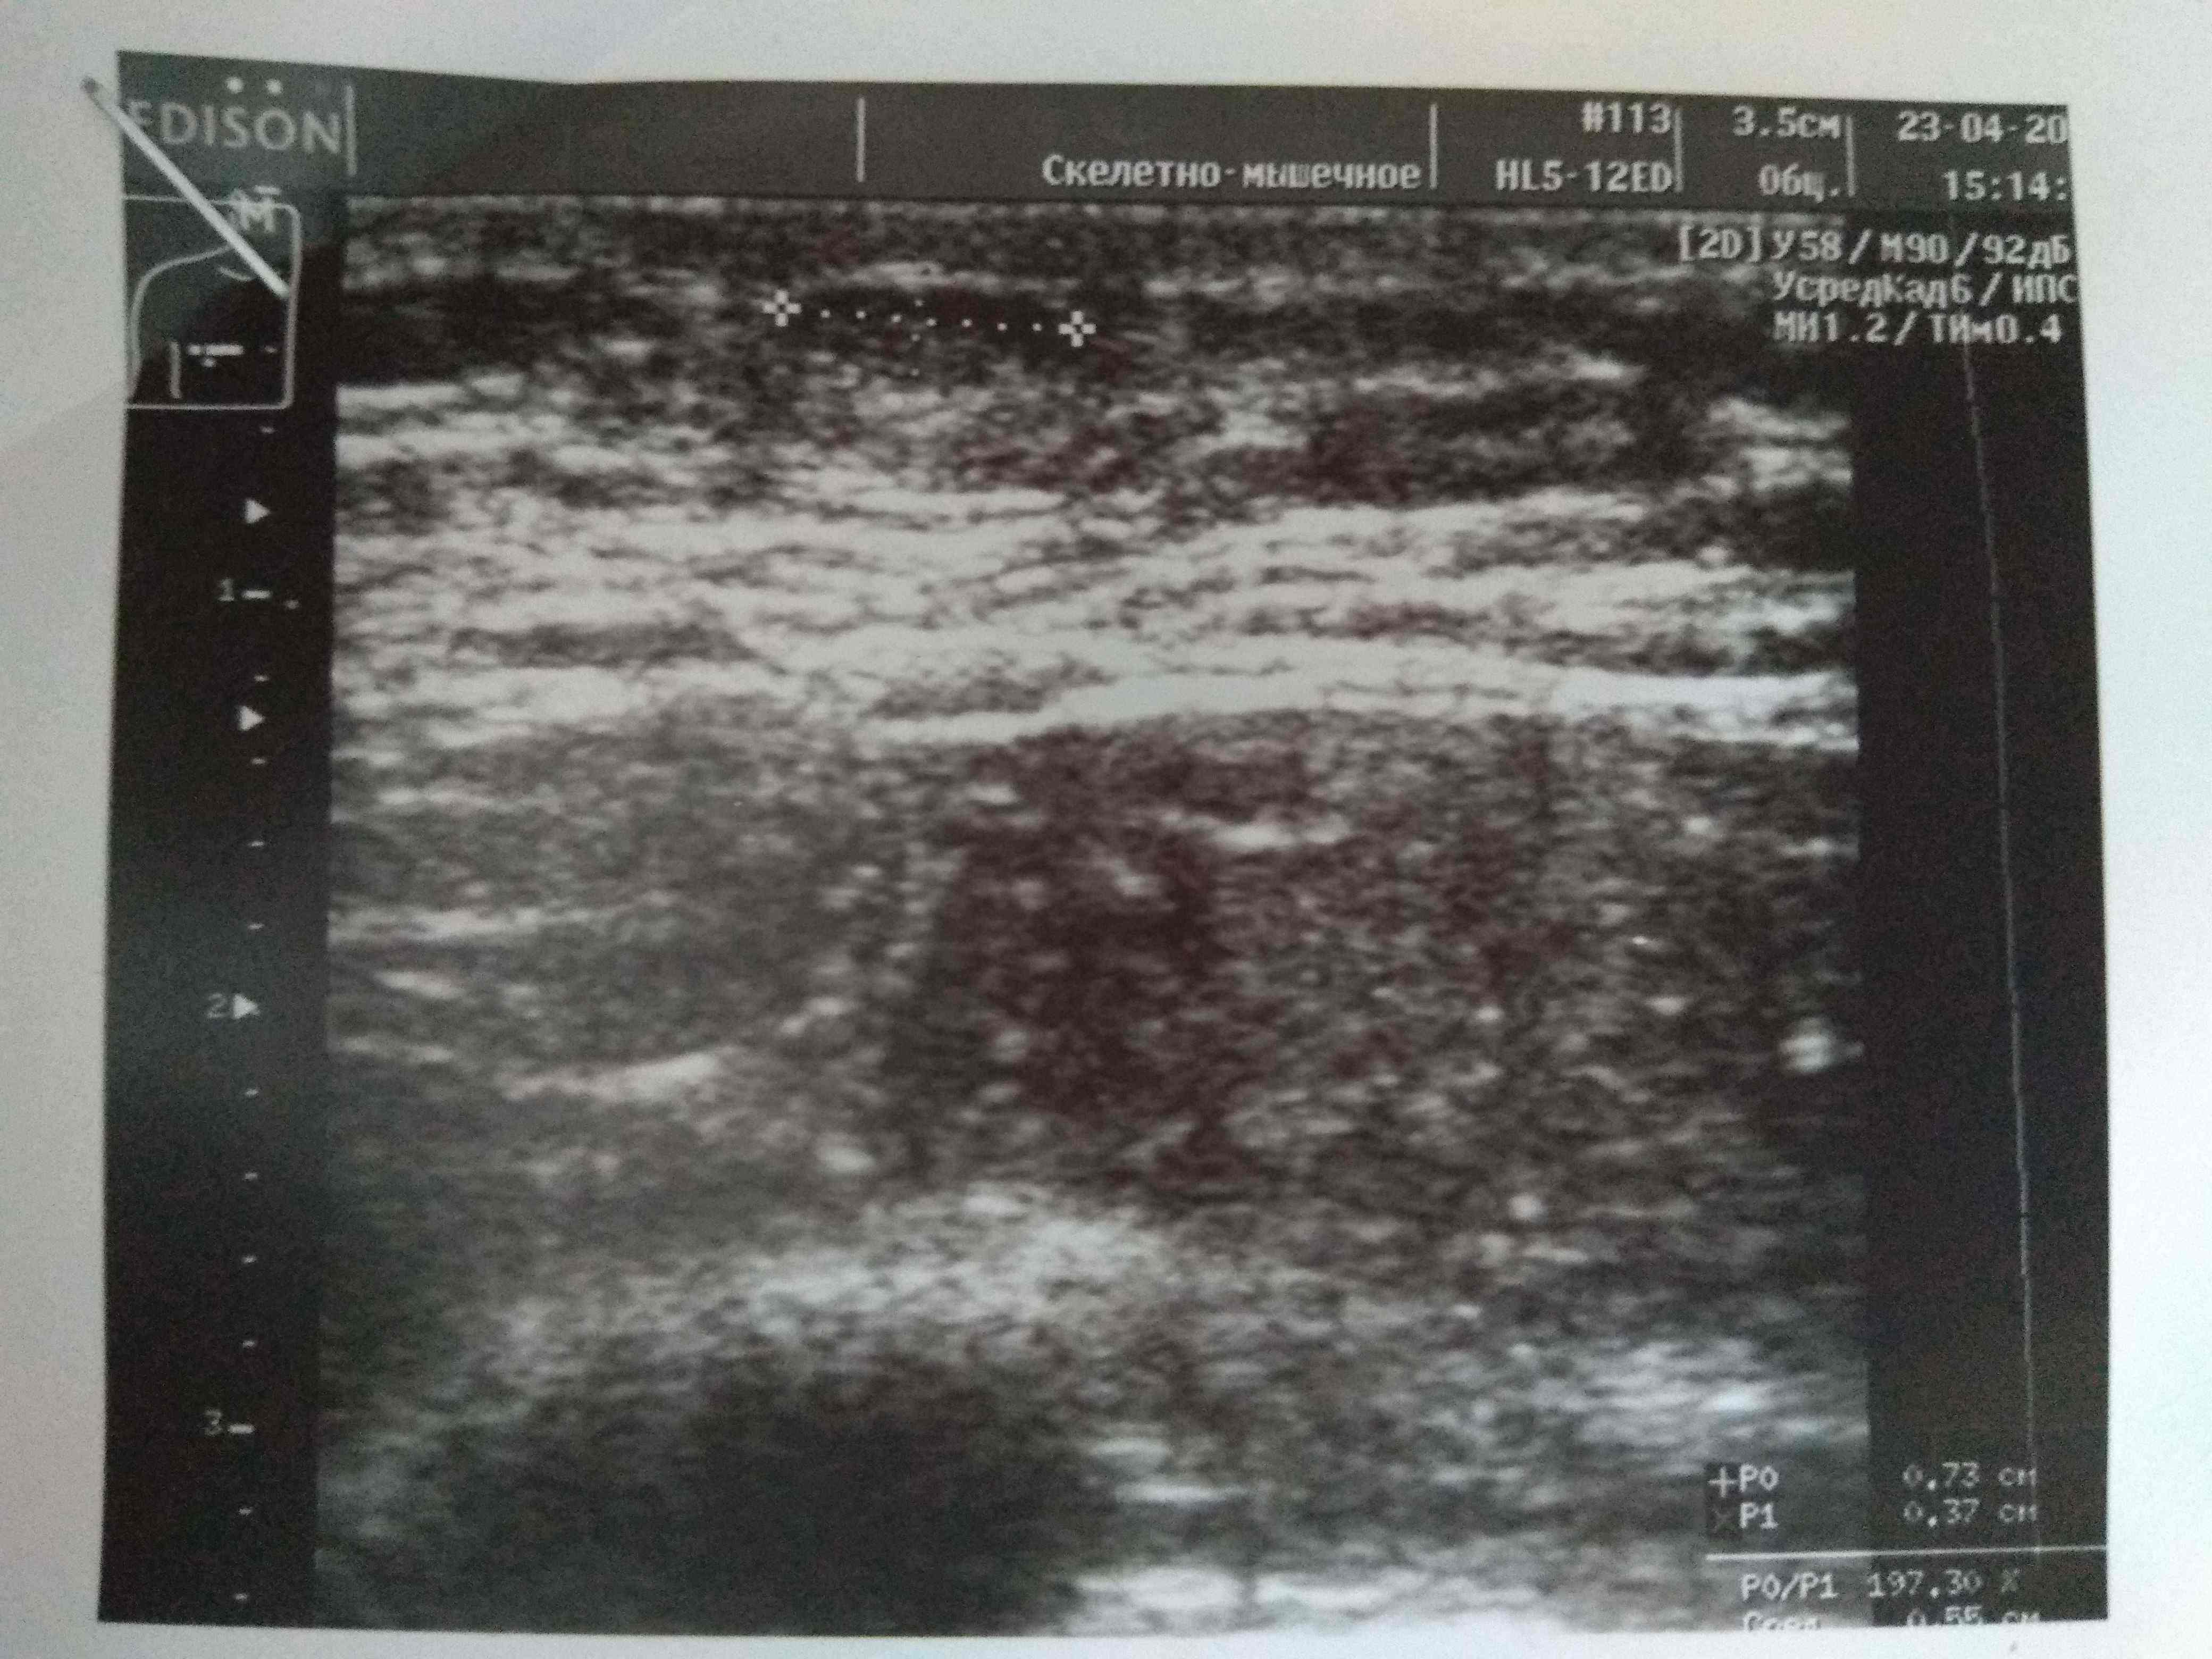

Ну да, железа увеличина.Посмотреть вложение 14714 Всем привет. Был курс нанфинил100+проп100. Набухли сиськи. Е2 и пролоктин в норме. PartyKill посоветовал сделать УЗИ .Результат: Эхо-признаки двусторонней геникомастии. Ну врачи привыкли всё драматизировать и слегка преувеличивать. Ну лечиться всё равно надо. Посоветуйте братья . До этого проблем с гино небыло.Может эта реакция на нанфинил такая? (Юзал первый раз)Хотя дека прошлым курсом нормально так вкатила.Стаж 4 года, ну разумеется с отдыхом , ПКТ, сдачей анализов. Всё по фэн-шую, всё как мы любим.Сейчас идёт мост , энка250 . Хотелось бы подлечиться а с июня снова в бой )) Выручайте